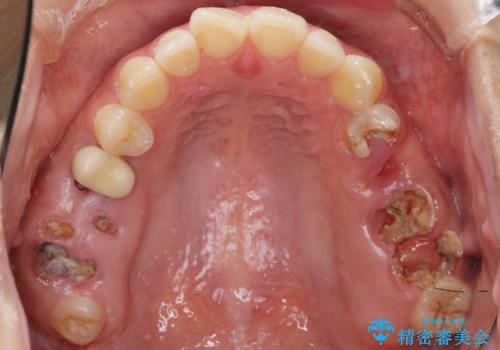

- う蝕により奥歯がボロボロになってしまい、咬むことができないことを主訴に来院された患者様です。

奥歯3本(左上567)はう蝕が深く保存不可能な状態であったため、やむなく抜歯しました。

インプラントも入れ歯も抵抗があるとのご相談により、自家歯牙移植を提案しました。

使っていない親知らず(左上8)を左上7抜歯窩に移植し、支台歯としてブリッジによる補綴治療を行いました。